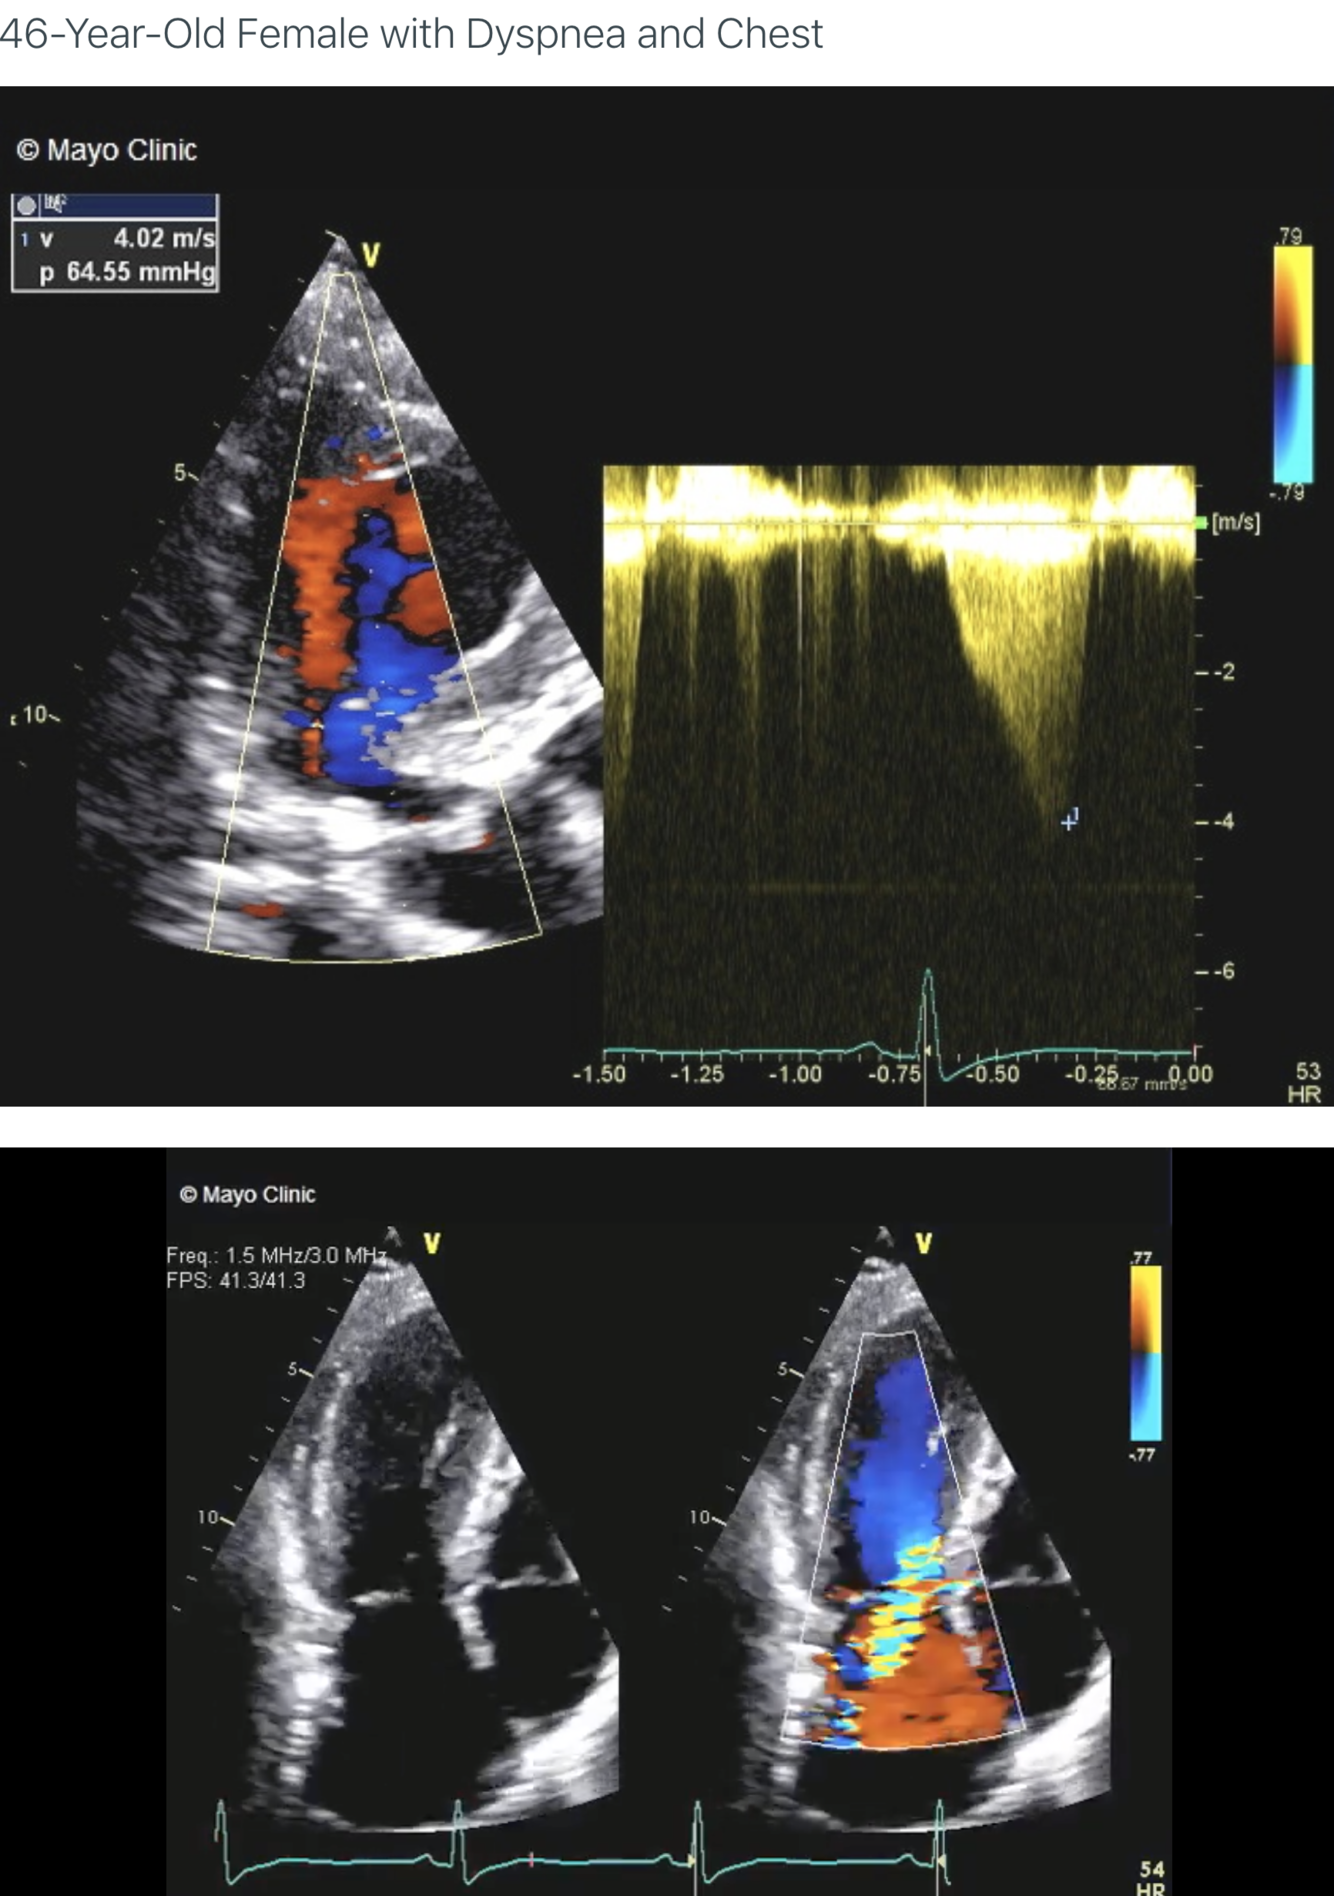

Describe the findings:

*****Dx: HCM with prior apical MI –> LV apical aneurysm

******mid-cavity obliteration during systole –> LVOTO

*******mechanism of MR in this setting –> systolic anterior motion of anterior MV